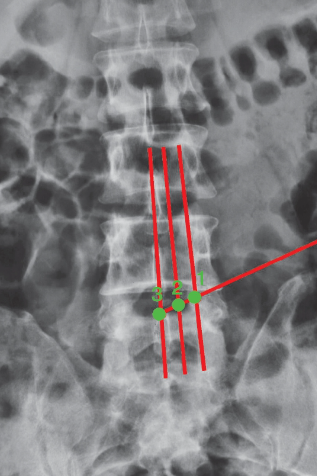

穿刺方向:线腰椎DR前后位上标出(图5)。

图5 腰椎DR前后位片穿刺方向线1.第一靶点;2.第二靶点;3.第三靶点

1.对于脱垂型腰椎间盘突出症这类型的病例,在穿刺点的设计时要更向头端。应用TESSYS技术-3靶点法中的穿刺点定位,以脱垂髓核基底部(L5椎体的后上缘)为靶点,穿刺方向线和穿刺角度线的交点来定。